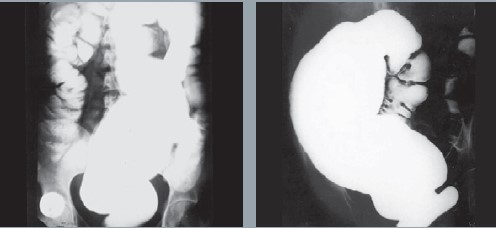

被克氏锥虫感染后,少数患者会发展为期4-8周的急性期。大约30-40%的感染者将随后发展慢性恰加斯心脏病和/或慢性恰加斯消化症状,通常10-30年后才会发病。恰加斯心脏病是发生在拉丁美洲的心脏病中最常见的病因,是流行地区中年人心血管疾病死亡的一个主要原因;慢性恰加斯病在胃肠道通常会导致巨食管或巨结肠症。